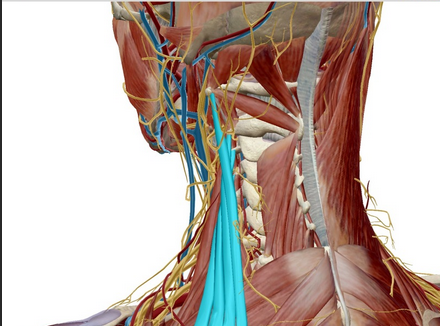

Die Haltemuskeln an den Querfortsätzen der Wirbelkörper stabilisieren die Wirbelsäule, machen die Feinabstimmung und führen kleine Bewegungen (Rotation, Seitneigung) aus. Die Hals- und obere Brustwirbelsäule ist das Punctum fixum bei Bewegungen im Schultergürtel und dem Schultergelenk. Im Gegensatz zum Beckengürtel, der knöchern geschlossen ist und somit für Stabilität in der unteren Körperhälfte sorgt, ist der Schultergürtel zwischen Schulterblatt und Hals-/Brustwirbelsäule offen und wird muskulär geschlossen, was eine Drehung des Schulterblattes ermöglicht und somit die Bewegungsfreiheit im Schultergelenk deutlich erhöht. Bei Überkopfarbeiten oder manuelle Arbeiten ohne aufgelegte Arme muss diese Muskulatur die Stabilität am Körperstamm leisten und ermüdet bei längerem Gebrauch (> 2–3 Stunden). Übermüdung ist immer mit Verkürzung (Schutzmechanismus der Muskeln) und Verspannung verbunden.

Bandscheiben sind die Druckpolster zwischen den Wirbelkörpern und ermöglichen — ähnlich wie bei einer Fahrradkette — eine Bewegung der sonst knöchernen Wirbelsäule vorwärts, rückwärts und seitwärts sowie eine Rotation. Bandscheiben haben keine Blutgefäße und ernähren sich durch Diffusion mit Nährstoffen aus der umgebenden Flüssigkeit. Ermöglicht wird das durch Druck und Sog. Wenn nun durch die Verspannung der Muskulatur ein Dauerdruck auf den Bandscheiben lastet kommt es zu Ernährungsstörungen — insbesondere des Faserringes, der den gallertartigen Kern ummantelt. Der Faserring reißt langsam ein, der gallertartige Kern wölbt sich an dieser Stelle vor und man spricht von einer/-m Bandscheibenprotrusion/-prolaps. Reißt er komplett durch kommt es zu einem Massenvorfall, der immer eine Akutintervention erfordert, da er auf das Rückenmark drückt. Bei Vorwölbung im Bereich des seitlichen Wirbelloches, wo der Rückenmarksnerv austritt kann es zu einer Kompression kommen. Bedingt durch die Lage der einzelnen Nervenfasern kommt es zunächst zu Schmerz, danach zu Gefühlsstörungen im Bereich des versorgten Gebietes (Dermatom) und letztendlich dann auch zu Muskellähmung, die immer eine sofortige chirurgische Intervention erforderlich machen.